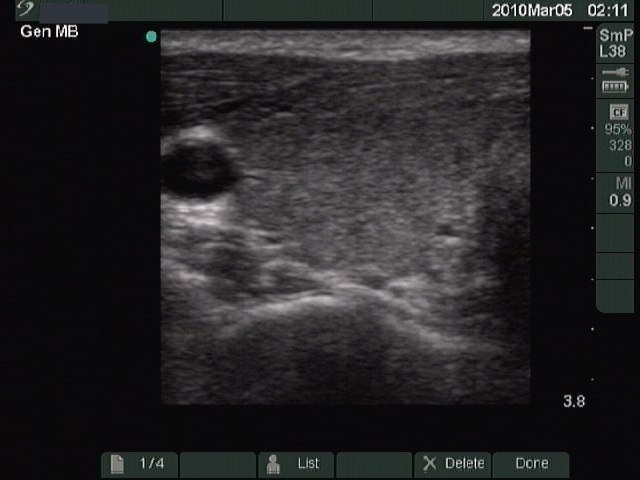

First examination (first row):

Clinical presentation: a 24-year-old man was referred for an evaluation of hyperthyroidism.

Palpation: no abnormality.

Functional state: hyperthyroidism with TSH 0.001 mIU/L, FT4 57.1 pM/L.

Ultrasonography: the thyroid was moderately hypoechogenic without any nodule. The vascularization was increased.Clinical diagnosis: hyperthyroidism caused by Graves-Basedow's disease.